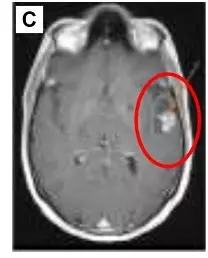

布加替尼最终停用并在2017年9月开始使用劳拉替尼(lorlatinib)治疗(100毫克,每日1次)。1个月后,中枢神经系统成像显示病灶减小了。

6个月之后显示病灶持续减小。在从布加替尼过渡到lorlatinib治疗后,他的系统性疾病保持稳定,甘油三酯水平仍正常但胆固醇升高至270mg / dL。